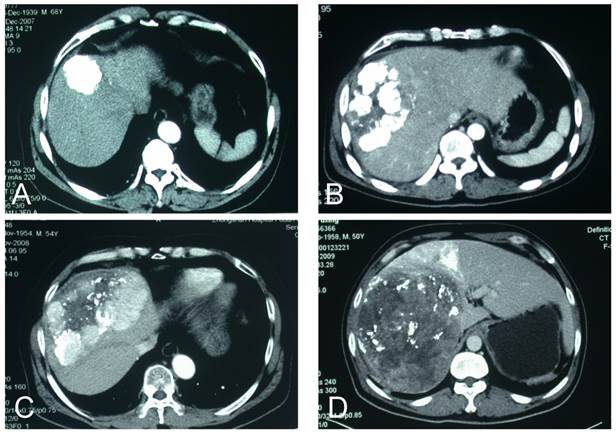

Traditionally, lipiodol accumulation patterns are classified into four types (type I, homogeneous; type II, defective; type III, inhomogeneous; and type IV, only slight accumulation)[5]. We used a simpler scheme of two types: type I, complete/intense accumulation and type II, low/moderate accumulation (Figure 1). We assessed lipiodol accumulation by CT before EBRT (4 weeks after the last TACE). We delineated the intrahepatic tumors and intratumoral lipiodol by non-contrast CT, measured the tumor volume (Vtumor) and the lipiodol volume (Vlipiodol), and then calculated the ratio of Vlipiodol / Vtumor. We categorized ratios >3/4 as complete/intense lipiodol accumulation and those ≤3/4 as low/moderate lipiodol accumulation.

CT scans of patterns of lipiodol accumulation after TACE. (a) Complete; (b) intense (>75% of tumor volume); (c) moderate (≤75% of tumor volume; (d) low.